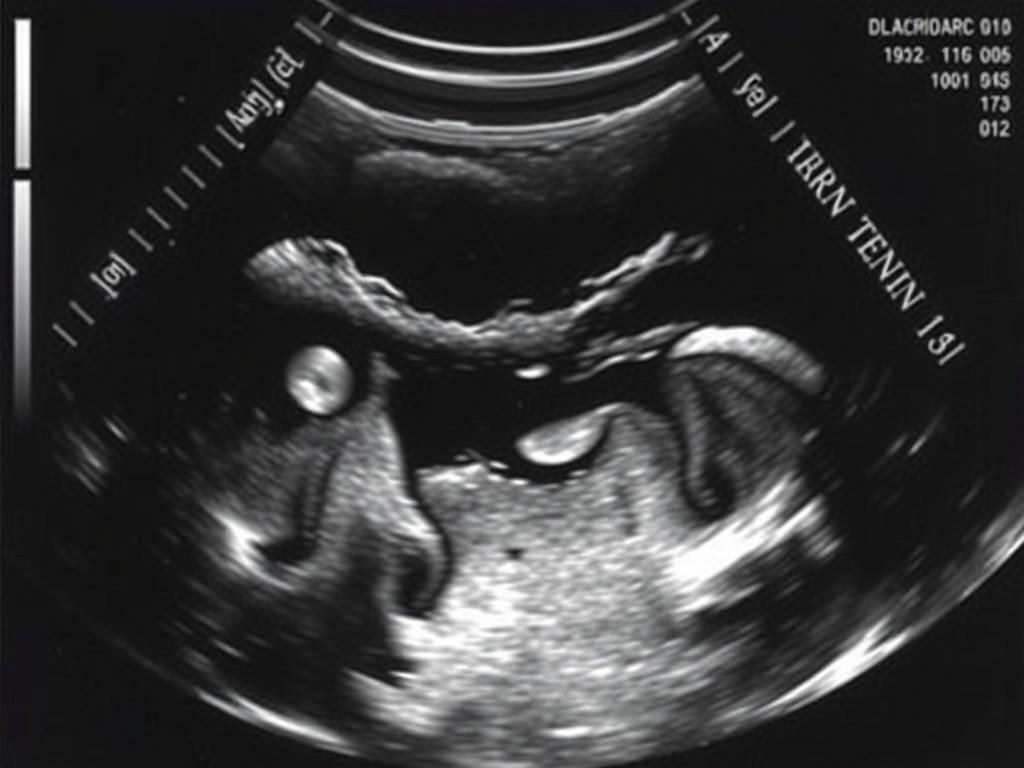

Что показывает УЗИ

Размер и структуру яичек. Состояние придатков. Наличие кист, узлов, камней и жидкости. Толщину оболочек. Кровоток в сосудах благодаря допплеру. Признаки грыжи. Следы травмы и разрыва. Врач видит и небольшие изменения, которые не прощупываются руками.

Чаще всего делают УЗИ с цветным допплером. Этот режим показывает ход крови по сосудам. Так врач отличает воспаление от перекрута, выявляет варикоцеле и оценивает питание тканей после травмы. В некоторых случаях помогает эластография. Она сравнивает плотность участка. Плотный узел требует большего внимания и иногда быстрой дообследования.

Гидроцеле. Это водянка. Между оболочками скапливается жидкость. Видно “черное озеро” вокруг яичка. Часто не опасно, но может мешать. Лечение подбирает хирург.